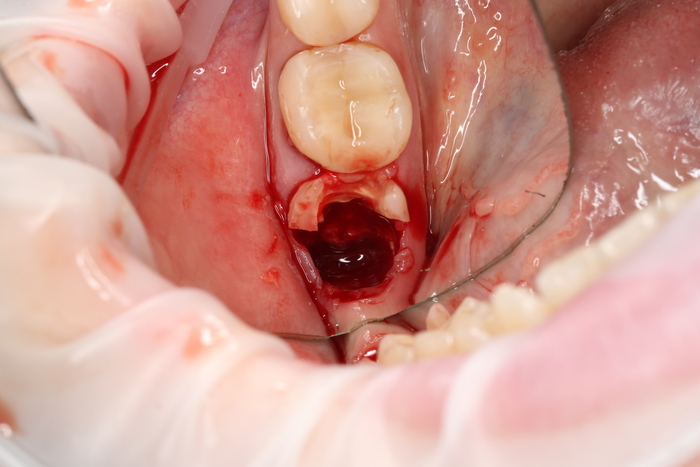

2 – проведение пластики десны.

Был взят трансплантат в области бугра верхней челюсти (это то место, где раньше был зуб мудрости).

3 – установка нового формирователя десны.

Далее проведена пластика десны, снова два месяца ожиданий и установка временной коронки:

Ну, такое, согласен, но это начало.